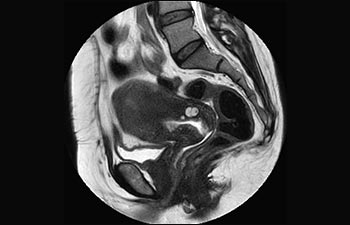

Frau Silvia Schiffer, leitende Radiologin bei Radiologie Schiffer in Deutschland, berichtet über ihre Erfahrungen mit dem Ingenia Prodiva 1.5T MR-System.